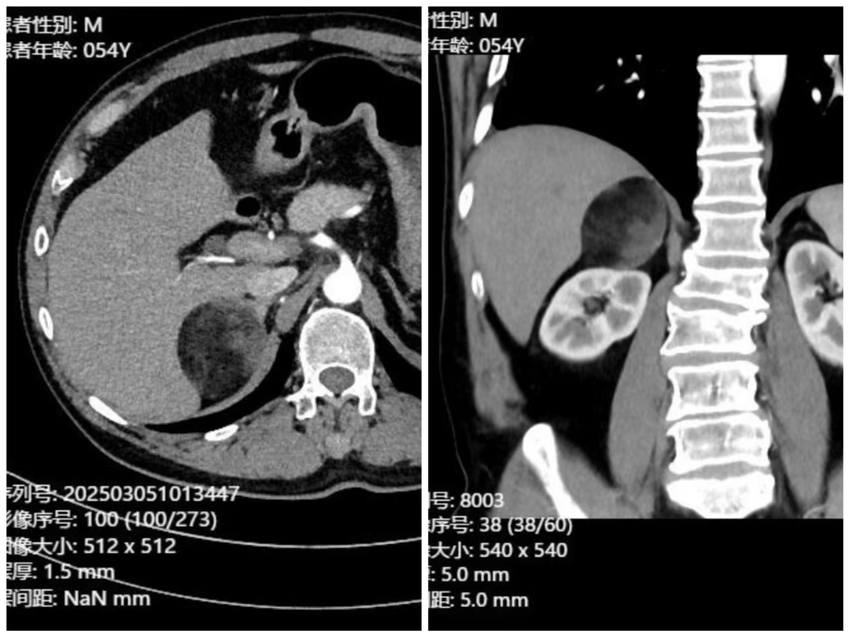

54岁的徐先生(化名),因右侧腰痛不适2月余入院就诊,检查发现右侧肾上腺巨大肿瘤,直径达7cm,予以收治入院。患者既往曾行腹腔镜下胆囊切除术,存在腹腔粘连,合并肿瘤解剖位置特殊,位于腹腔的深处,被结肠、十二指肠、肝脏等器官覆盖,又临近下腔静脉等重要血管,手术难度很大,就像是在刀尖上跳舞。

为确保患者手术安全,泌尿外科主任方统文、副主任董恩文联合影像科、麻醉科、心血管内科等科室进行详细术前评估,制定了个性化的手术方案,最终决定采取腹腔镜下肾上腺肿瘤切除术进行治疗。